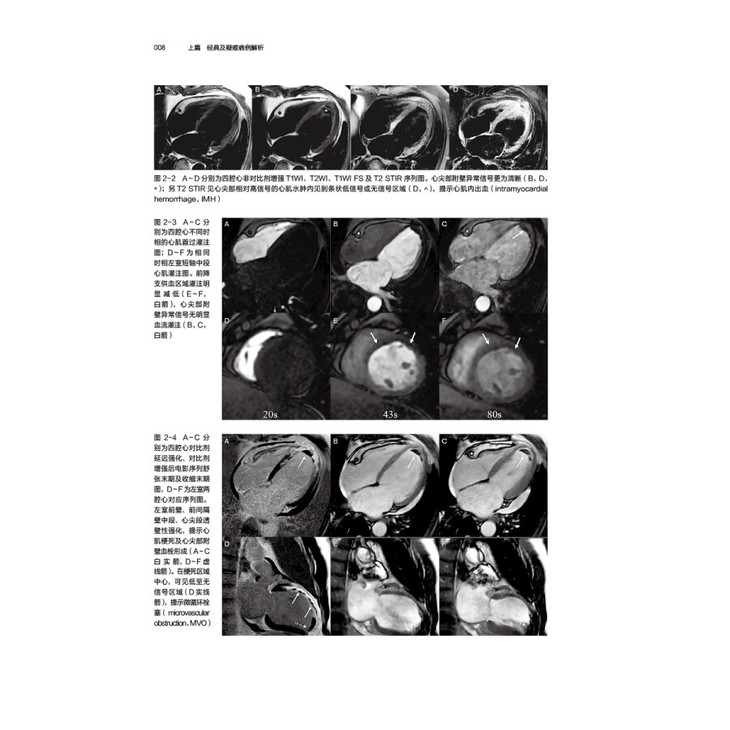

病例1冠心病,急性心肌梗死

病例2冠心病,急性心肌梗死(微循环障碍)